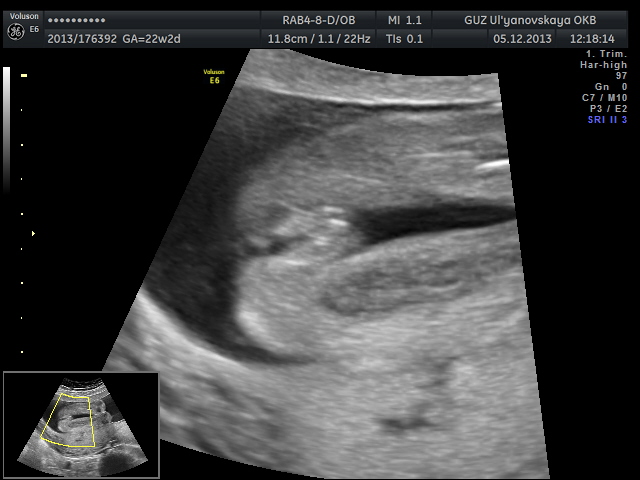

Результаты: УЗИ, КТГ, доплера, скринингаБыли мы сегодня с мужем на узи. Срок 22-23 недельки. Наша умничка спала головкой вниз и дала себя рассмотреть со всех сторон. Врач сказала, что для такого срока редко, чтобы детки так хорошо лежали. Удачно. По узи у нас всё хорошо. Сроки сходятся.

Вот несколько фото. Видео не загружается здесь, а выкладывать малышку на ютуб не хочу.

Дальше...... Наш "пирожок" во весь экран.